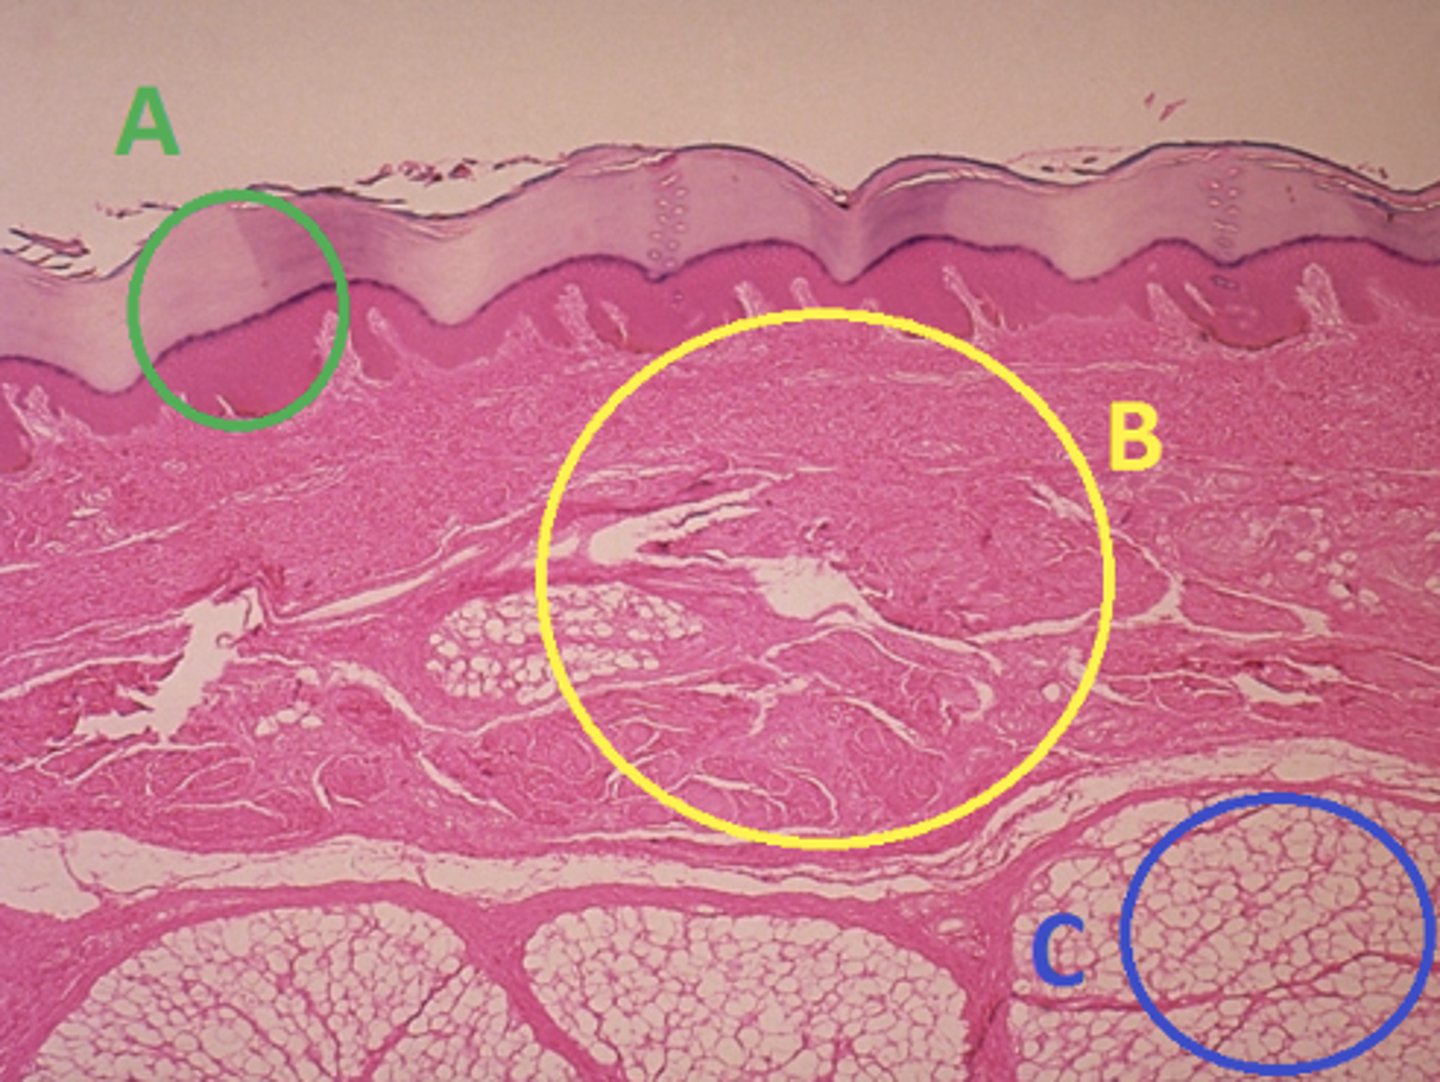

C - hypodermis

Answer the following questions based on the features indicated in the following image. Which letter indicates the administration site for subcutaneous injections?

A - epidermis

Answer the following questions based on the features indicated in the following image. Which letter indicates the administration site for topical creams and ointments?

B - Dermis

Answer the following questions based on the features indicated in the following image. Which letter indicates the administration site for the tuberculin skin test?

A - epidermis

Answer the following questions based on the features indicated in the following image. Which letter indicates a region of the skin with no nerves or blood vessels?

B - Dermis

Answer the following questions based on the features indicated in the following image. Which letter indicates the region where skin appendages (sweat glands, sebaceous glands, and hair follicles) have their roots?

Epithelial tissue

Answer the following questions based on the features indicated in the following image. Which of the four major tissue types is indicated by letter A?

Which letter indicates the administration site for insulin injections?

A

Which letter indicates the administration site for a lidocaine patch?

B

Which letter indicates the administration site for an allergy test?

B

Which letter indicates a region of the skin rich in dense, irregular connective tissue?

C

Which letter indicates the region most important for energy storage and thermal insulation?

Connective

Which of the four major tissue types is indicated by letter C?

Skin of the dorsal surface (back) of the hand

Which part of the body could the previous image represent?

Skin of the ventral surface (palm) of the hand

Skin of the dorsal surface (back) of the hand